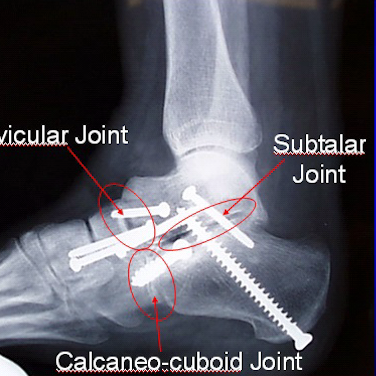

Deformity Correction Cavus Foot Reconstruction Cavus Foot Reconstruction Triple Fusion Triple Fusion Charcot Beaming Charcot Beaming Double Fusion Double Fusion Flatfoot Reconstruction Flatfoot Reconstruction Subtalar Fusion Subtalar Fusion